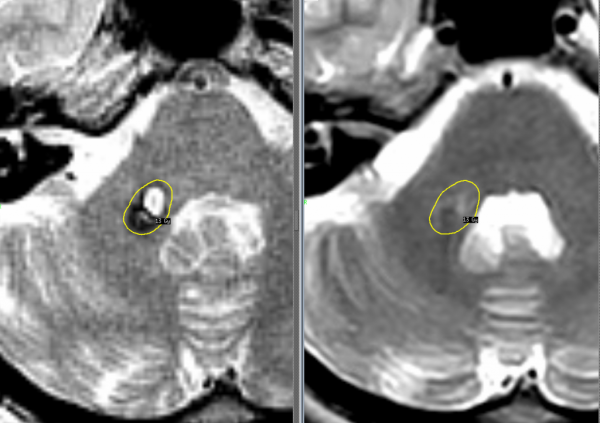

Во время диагностики ангиом следует проанализировать наличие симптомов, факторов и риска и уделить внимание семейной предрасположенности к онкозаболеваниям. Зачастую ангиома сосудов мозга — случайная находка во время компьютерной томографии (КТ). Этот метод неинвазивен, но не специфичен и значим только для опухоли большого размера.

Подтверждается диагноз гемангиомы мозга на основе аппаратного обследования – КТ или МРТ черепа.

МРТ (магнитно-резонансная томография) служит методом выбора для диагностики данной патологии, так как он гарантирует стопроцентную точность.